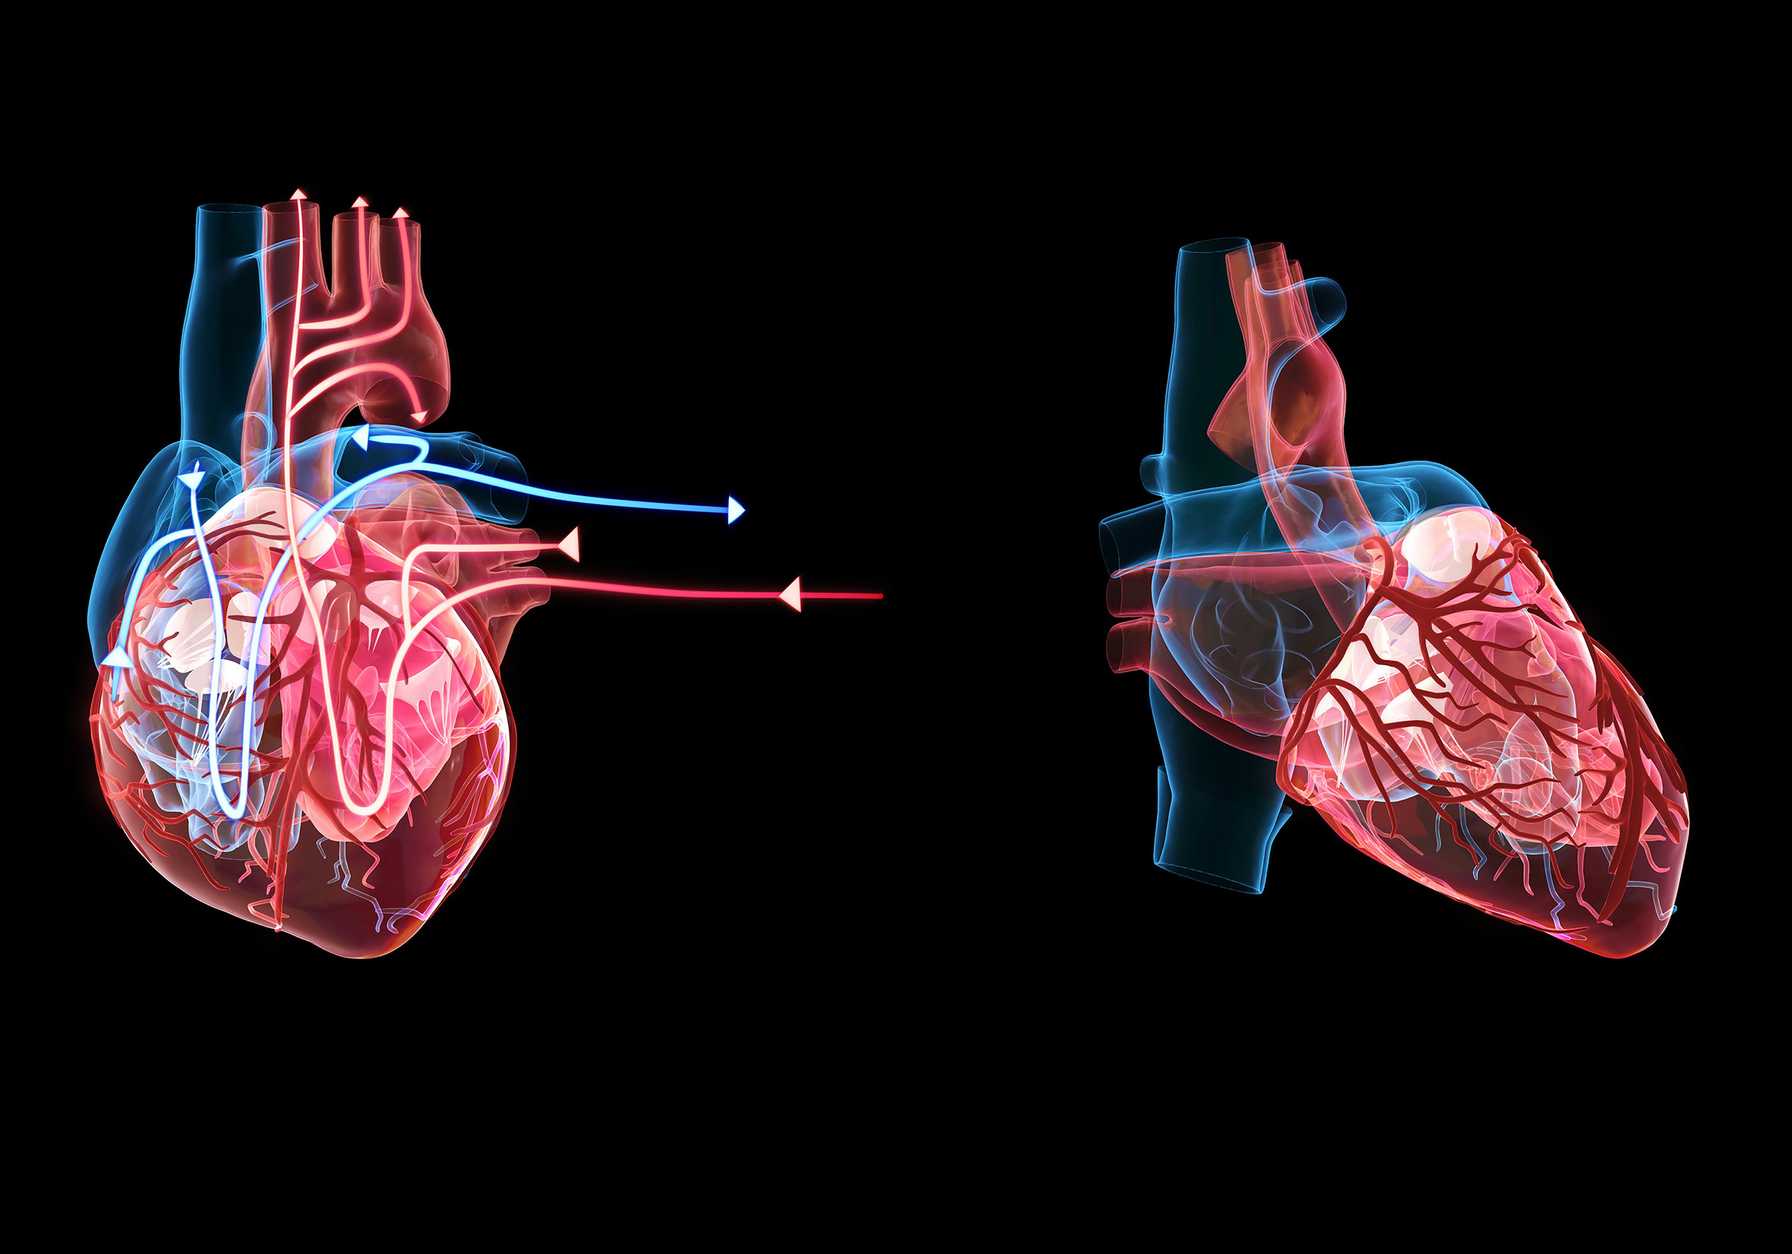

In 2024, Montefiore Einstein Cardiology advanced its leadership in cardiac care and research, making groundbreaking strides in heart transplantation, structural valve interventions and arrhythmia management, while also expanding its state-of-the-art imaging program. This commitment to innovation, alongside significant contributions to scientific research and global education, underscores Montefiore Einstein's dedication to providing the highest quality of care.

9.9%

HTx 1-year survival